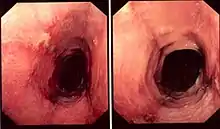

| Pathology image of lymphocytic esophagitis (H&E stain). The image demonstrates common findings in the condition: dense peripapillary lymphocytic infiltrate with spongiosis (arrow), and absence of neutrophils and eosinophils. | |

While the diagnosis of lymphocytic esophagitis depends on the biopsy results, certain changes can be visualized directly at the time of endoscopy. The esophagus may be narrow in calibre,[5] may show multiple rings,[5] redness,[5] linear furrows[1] or the mucosal lining may slide demonstrating a "crepe-paper" appearance.[1] Complications such as strictures of the esophagus can also be detected with endoscopy.[5] These changes are very similar to those found in eosinophilic esophagitis, a more common and better understood esophageal disorder thought to be of allergic origin.[5] Narrow-band imaging with magnification endoscopy is another imaging modality that can show characteristic changes of lymphocytic esophagitis.[7]